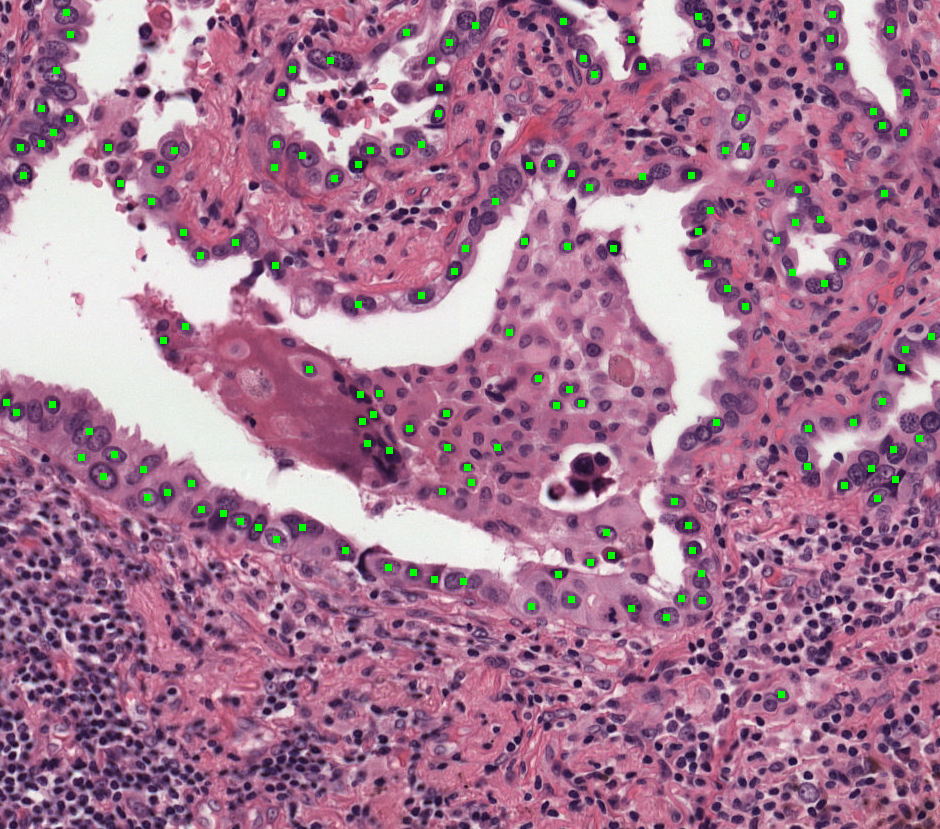

Refer to caption

(a) Ground Truth1

(b) Prediction1

(c) Ground Truth2

(d) Prediction2

Figure 5: Visual comparison of ground truth and UAM predictions on the IGNITE dataset. Tumor cells are highlighted in green.

Visualization and AI Interpretability. As illustrated in Figure 5, UAM effectively highlights tumor cells on H&E slides based on radiomics data, facilitating pathologist interpretation and enhancing AI explainability.